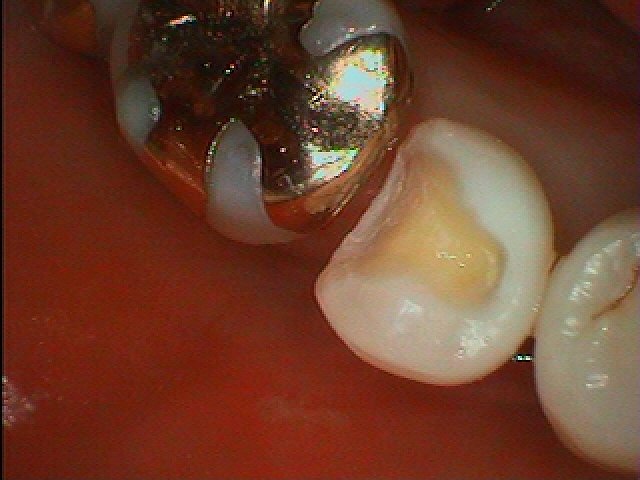

銀歯をすべてセラミックへやり変えていきます セラミックを用いた臨床例 審美治療|お知らせ |広島市安佐南区の歯科医院 銀歯をすべてセラミックへやり変えていきます セラミックを用いた臨床例 審美治療 トップ お知らせ・ブログ お知らせ 銀歯をすべてセラミックへやり変えていきます セラミックを用いた臨床例 審美治療 銀歯をすべてセラミックへやり変えていきます セラミックを用いた臨床例 審美治療 左上の6番部になります この銀歯を外して虫歯治療を行っていきます 中はこのようになっていました 近心部の虫歯を除去していきました CR樹脂にて覆罩を行っています セレックセラミックにて修復しています 銀歯が外れたとのこと わずかに虫歯が存在していました セレックセラミックにて修復しています 綺麗に仕上がりました Web診療予約 初めての方へ 選ばれ続ける理由 院内設備について 歯が痛いしみる一般歯科 歯がぐらぐらする歯周病 健康な歯を保ちたい予防歯科 子供の虫歯予防をしたい小児歯科 銀歯をセラミックに審美歯科 白い歯を目指しませんか?ホワイトニング 矯正専門医がいるので安心矯正歯科 抜けた歯を補いたいインプラント・入れ歯 医院案内 スタッフ紹介 メリィハウス歯科クリニックオフィシャルホームページ ラベンダー歯科クリニックオフィシャルホームページ お知らせ・ブログ ホーム 診療科目 一般歯科 歯周病治療 予防治療 小児歯科 審美治療 ホワイトニング 矯正歯科 入れ歯・インプラント マウスピース矯正 初めての方へ 院長・スタッフ 設備紹介 医院案内・アクセス メニューを閉じる